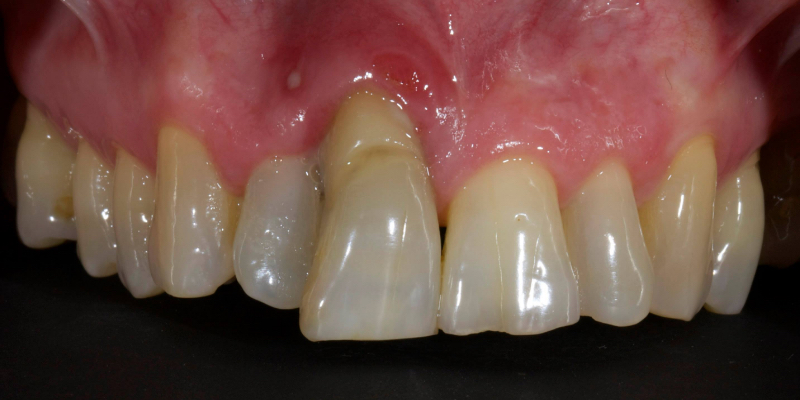

Take Arthur, a 76-year-old man who presented with a vertical root fracture of his upper left central incisor. His medical conditions precluded his request for an implant, so he agreed to the proposal for an adhesive bridge instead.

The tooth was extracted and for four months the pontic site was conditioned with a removable Essix-type of denture (Fig. 1).

An e.max (lithium disilicate), one-wing (adjacent central being the retainer) bridge was placed, which resulted in an acceptable outcome (Figs. 2-4) that was more timely and at a lower financial and biological cost to the patient than the implant Arthur initially thought he wanted.